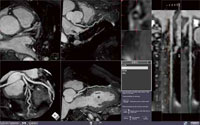

s ziostation2のMRアプリケーション ─ さまざまな目的に対応するMR解析機能

3D医用画像処理ワークステーション「ziostation2」には豊富なMRの心臓解析アプリケーション類が搭載された。標準機能の1つであるマルチデータフュージョンでは,Whole heart coronary MR のVR画像に遅延造影画像を重ね合わせたフュージョンも可能で,低侵襲なMRIで心筋シンチグラフィのように心筋の血流状態を視覚的に確認できる。このほか,多数の機能について現在,米国や日本国内の施設において共同研究が進められており,その充実ぶりがうかがえ,今後のさらなる充実にも期待できる。以下にRSNAで紹介された新機能を中心に紹介する。

MR冠動脈解析

画面の操作環境が一新され,定評のあるziostation2のCT冠動脈解析のインターフェイスが適用された。さらに,血管の中心線抽出の精度や速度,修正時の操作性が向上している。血管抽出の精度が向上したことにより,複数の血管パスを利用して多曲面をMIP投影するFlex Surface MIPの作成も簡便になり,広範囲の冠動脈の観察をサポートしている。